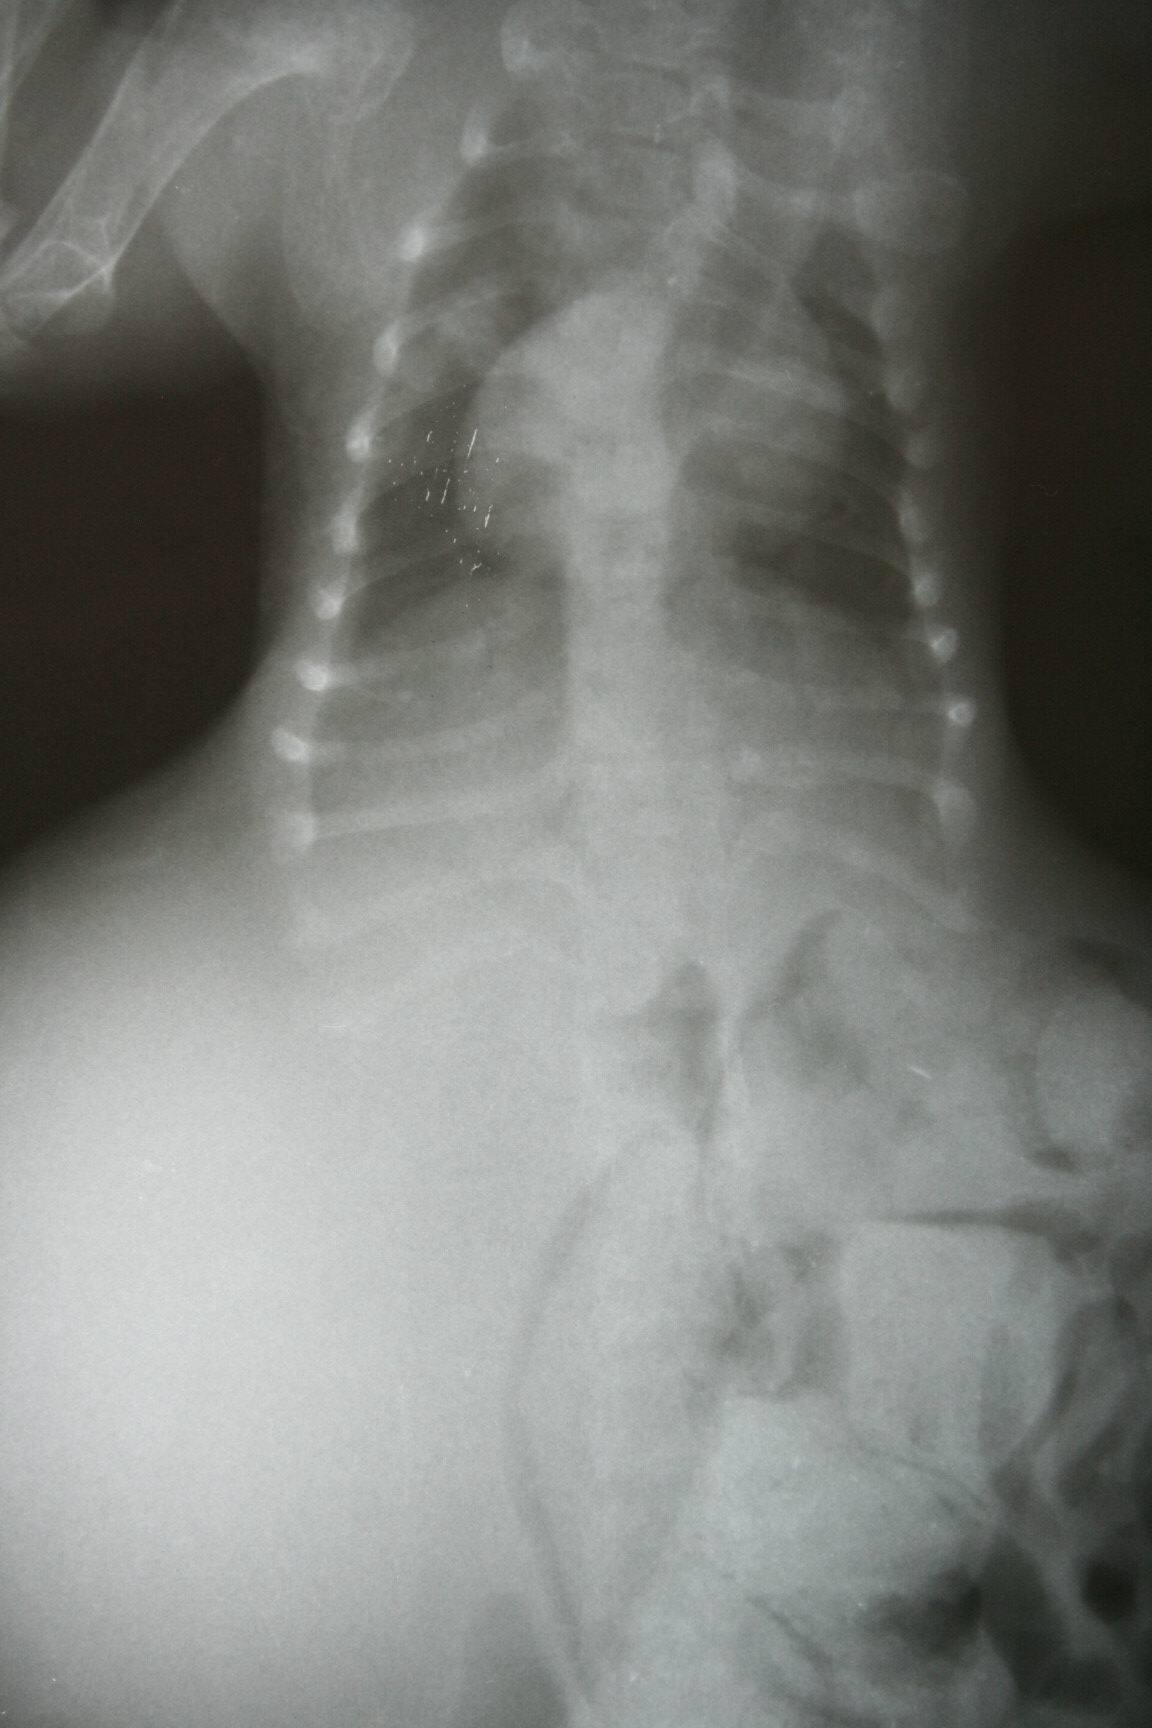

醫生診斷∼可能是車禍或是外力所造成..第11-13胸椎有斷裂..第2-3 腰椎有斷裂..無法自行排便及排尿..已先幫助擠尿及通便.針灸治療..目前出院瑤媽接手後續照護..小橘子好乖.雖然生病還是一直呼嚕.愛抱抱.請大家幫幫忙.慷慨解囊..小橘子還小.希望能熬過這關卡...感謝大家.感恩^^~

5.1/18∼X光片2張400X2= 800

6.1/19∼X光片2張400X2= 800

( 再次 確診大便 排出 及脊椎 斷裂處)